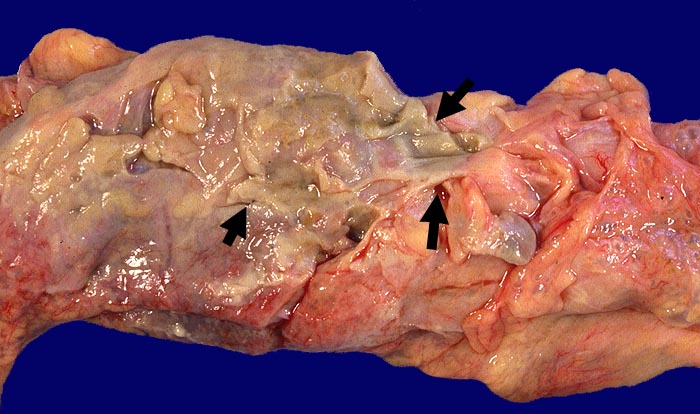

PathoPic ID 295 - Fibrinös eitrige Peritonitis bei perforierter Sigmadivertikulitis

Fibrinös eitrige Peritonitis bei perforierter Sigmadivertikulitis

Schmutzig grau-gelbe

►

Auflagerungen auf der Serosa.